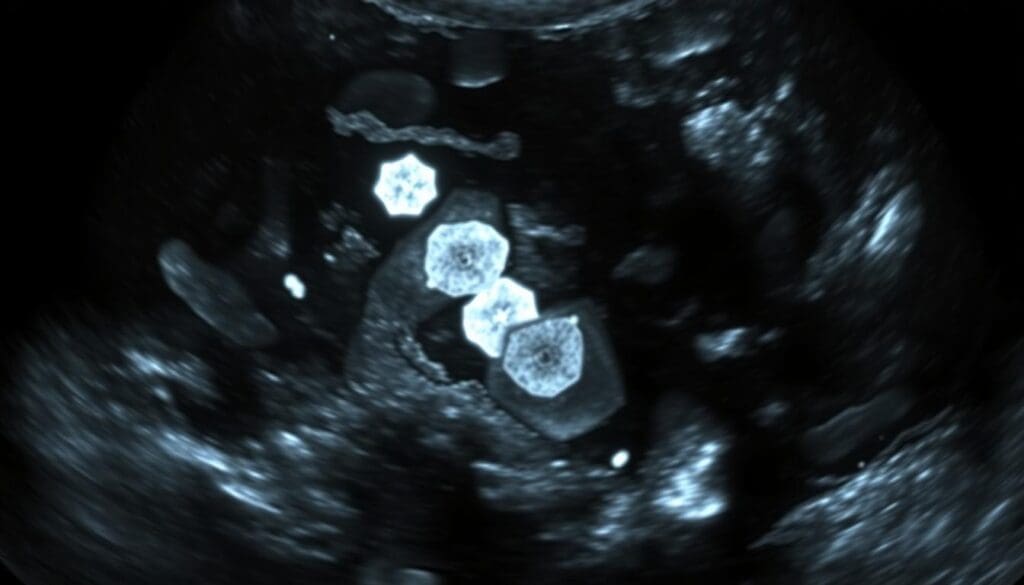

Microcalcifications Breast Ultrasound: Applications and Limitations

Even though mammography is the top choice, breast ultrasound is useful for certain cases, like dense breasts. Ultrasound helps check for any masses or lesions nearby.

We use ultrasound to look closely at calcifications found on mammograms, if we think there might be a mass. But, ultrasound can’t find tiny calcifications as well as mammography can.